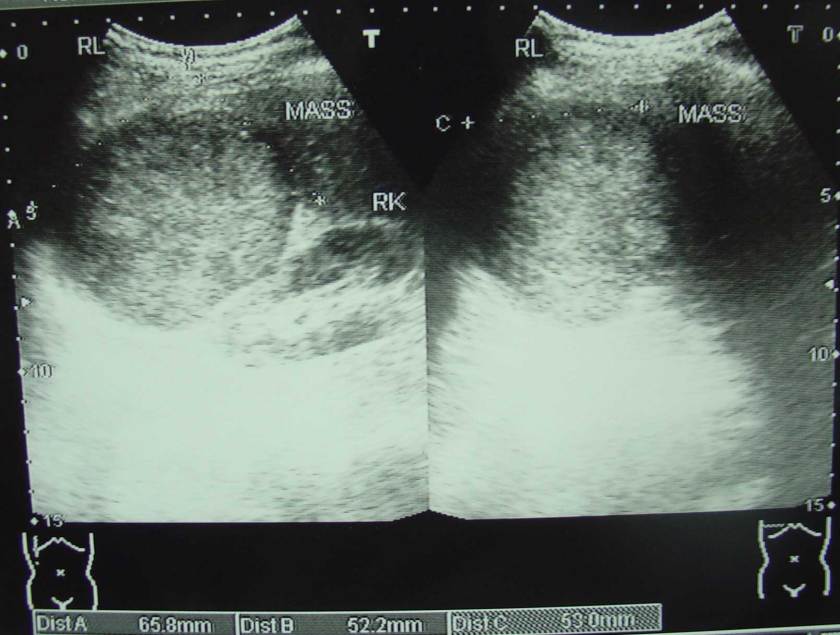

Goh adalah seorang pria berusia 75 tahun dari Indonesia. Ia menjalani pemeriksaan medis pada tahun 2008 dan dokter menemukan SGOT (AST) meninggi, mengindikasikan ada sesuatu yang tidak beres di livernya. Goh melakukan ultrasonografi dan hasilnya adalah terdapat tumor pada lobus kiri liver nya sebesar 6,3 x 8,9 cm.

Setelah kembali ke Indonesia, Goh diberitahu tentang sebuah rumah sakit di China. Goh pergi ke China. Sekali lagi dokter menyarankan untuk operasi. Dan sekali lagi dokter menyarankan untuk dioperasi. Goh menolak kembali. Bagaimanapun juga, ia setuju untuk melakukan kemoembolisasi. Ini menghabiskan biaya sekitar 10.000 RM. Setelah terapi kemo, Goh kembali ke indonesia. Sekitar satu bulan kemudian, ia kembali ke China untuk terapi kedua. Tetapi, pada saat pemeriksaan, dokter memberitahu Goh kalau kemoembolisasi yang dilakukan sebelumnya tidak efektif. Terapi lebih lanjut dibatalkan. Goh kembali ke Indonesia dan mulai mengkonsumsi suplemen. Ia juga memonitor AST nya secara reguler selain melakukan USG. Nilai AST dan ukuran tumor terus meningkat. USG yang dilakukan pada 12 Maret 2009 (dibawah) mengindikasikan tumor berukuran 9,7 cm x 8,0 cm.